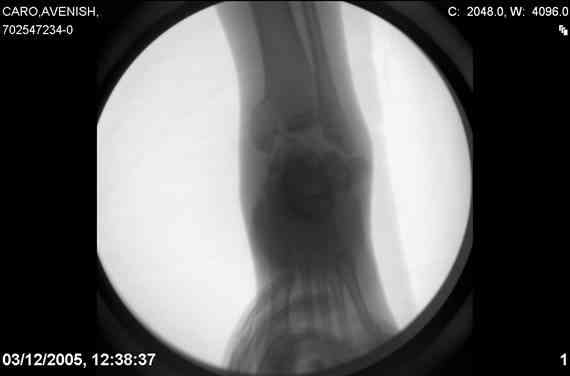

ya by popytalsya sobrat talus anatomichno,seichas pozdno operirovat iz za oteka,po etomy distrakziya apparatom budet optmalna.Posyalu vam podobyai moi sluchai.

14 years old girl

Fall from height ( 3rd floor)

Compressed fractures of L1-L2

Fx of orbital bone

Дорогие Mark Eidelman and A. Liberson. Спасибо за представленные иллюстрации и за дельные советы.

Mark, судя по снимкам в день поступления произведен А.В.Ф., а остеосинтез ч-з какое время произведен?, остеосинтез произвели открытым способом?( на снимке п/о рубцы).

aparat postavlen v den postupleniya,rastaynuli, vpravili zakryto naskolko vozmoghno, a kogda otek spal sdelali otkrytoe vpravlenie.Teryat tut nechego, moghno tolko uluchshit.